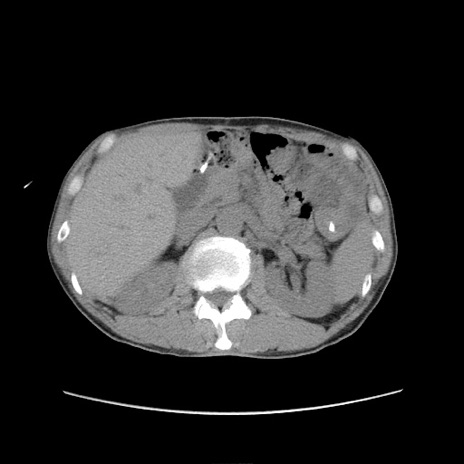

症例11(横断像)

【症例】 60歳代男性

【主訴】 下腹部痛

【現病歴】 本日夜中より下腹部痛の症状認め、受診。

【既往歴】 膀胱癌(膀胱全摘+尿管皮膚瘻術) 、胃癌術後

【身体所見】 BT 35.3℃、PR 58/min、BP 136/98mHg、腹部平坦、軟、腸蠕動音±、ストマ留置あり、左上腹部~正中部に圧痛あり、反跳痛なし。

【データ】WBC 5100、CRP0.01